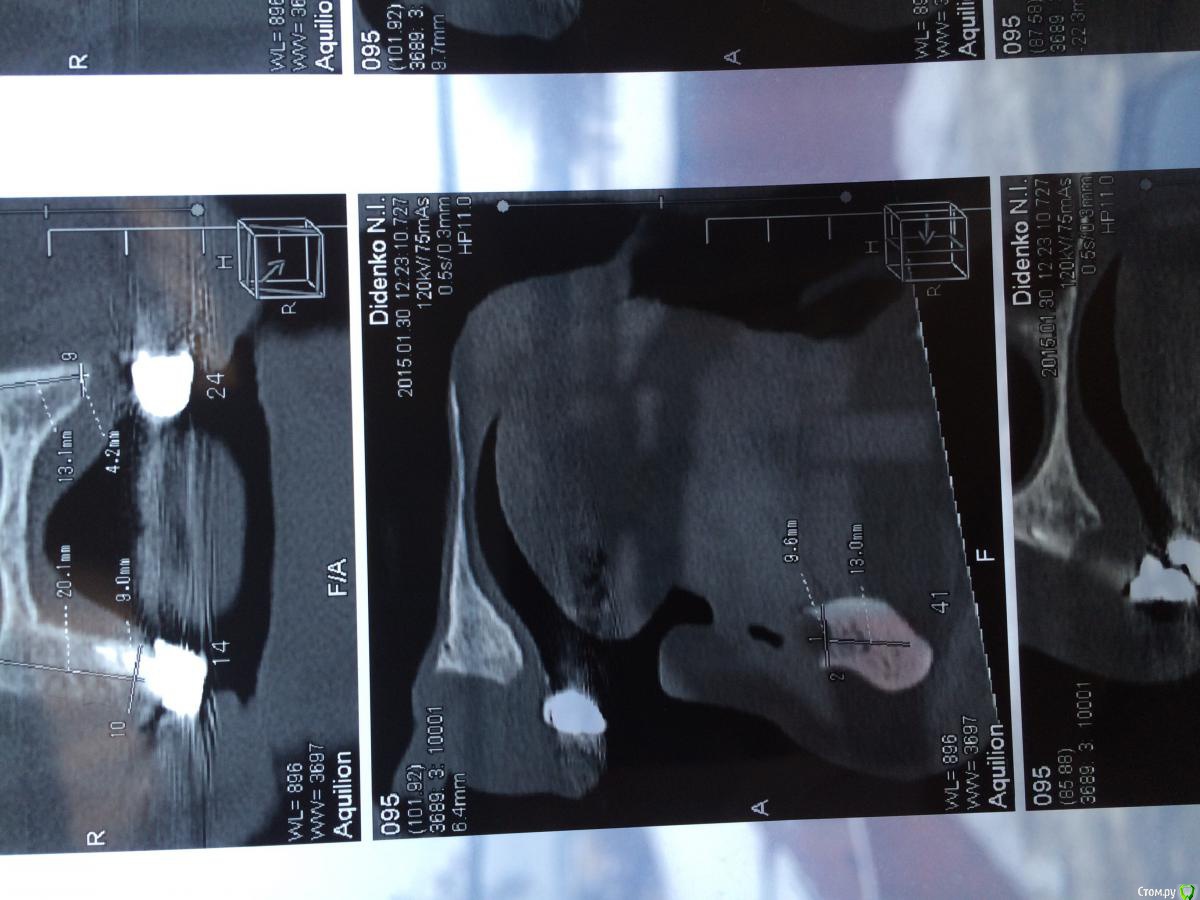

urseva19.05.10 Опубликовано 31 января, 2015 Поделиться Опубликовано 31 января, 2015 Коллеги, в каких позициях на ваш взгляд целесообразнее поставить имплантаты желательно без НКР ( пациент ограничен во времени) что бы в последствии протезироваться съемным протезом на локаторах? На верх не смотрите там все ясно Спасибо! Ссылка на комментарий

faity Опубликовано 4 февраля, 2015 Поделиться Опубликовано 4 февраля, 2015 выровнить гребень и сделать НКР это не одно и тоже. для съемника на локаторах нужен одинаковый уровень винтов и биотип не менее 3-х мм. гребень можно просто выровнять до одинаковой высоты, ямы присыпать придется, десну можно выростить при необходимости.а почему именно локаторы? не хотите балку на 6-ти винтах? условия вроде позволяют Ссылка на комментарий

urseva19.05.10 Опубликовано 4 февраля, 2015 Автор Поделиться Опубликовано 4 февраля, 2015 выровнить гребень и сделать НКР это не одно и тоже. для съемника на локаторах нужен одинаковый уровень винтов и биотип не менее 3-х мм. гребень можно просто выровнять до одинаковой высоты, ямы присыпать придется, десну можно выростить при необходимости.а почему именно локаторы? не хотите балку на 6-ти винтах? условия вроде позволяютСказать честно, может и хочу но с балками ни разу не работал и в лаборатории у нас не делают. Да и экспериментировать с этим пациентом не очень охота. Спасибо за совет. Ссылка на комментарий

red_butler Опубликовано 7 февраля, 2015 Поделиться Опубликовано 7 февраля, 2015 на шести можно и не съемный сделать Ссылка на комментарий

urseva19.05.10 Опубликовано 7 февраля, 2015 Автор Поделиться Опубликовано 7 февраля, 2015 на шести можно и не съемный сделатьПотихоньку задумываюсь об этом. В области каких зубов думаете без нкр получиться? Ссылка на комментарий

АнтонТЛТ Опубликовано 9 февраля, 2015 Поделиться Опубликовано 9 февраля, 2015 Потихоньку задумываюсь об этом. В области каких зубов думаете без нкр получиться?ширина достаточная, так что практически в любом месте можно поставить короткие имплантаты Ссылка на комментарий